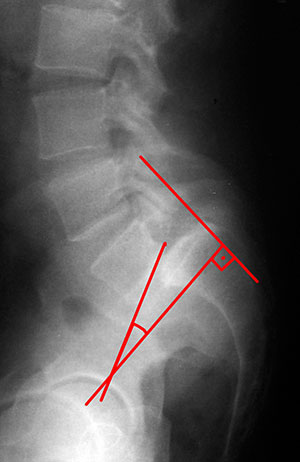

Devem ser realizadas Radiografias colimadas em AP e perfil da região lombosacra. No Rx em perfil é possível avaliar o grau de escorregamento de acordo com a classificação de Meyerding18. Pode-se ainda avaliar o chamando ângulo de escorregamento

Ângulo de escorregamento

Desenha-se uma linha perpendicular ao aspecto posterior do sacro e outra ao longo da borda inferior da vértebra de L5. Um valor positivo alto para o ângulo de escorregamento (em geral maior que 45 graus) indica que a vértebra L5 esta muito inclinada aumentando suas chances de escorregar9. Outro ângulo que pode ser analisado é o chamado ângulo de inclinação sacral (figura 7), que corresponde ao ângulo entre uma linha traçada na parte posterior do sacro e uma linha vertical. Para este ângulo valores maiores que 55 graus tem maior risco para progressão9.